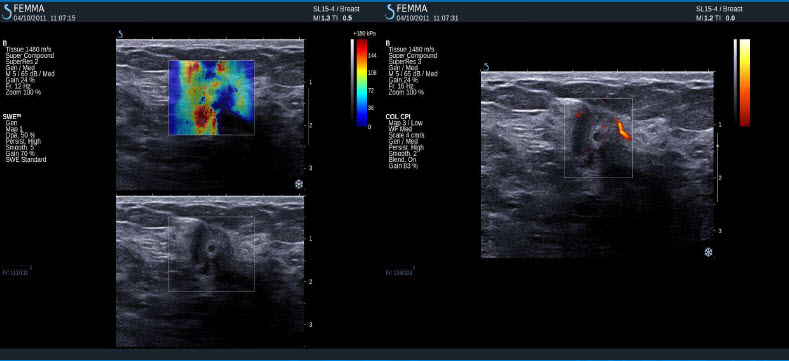

Negativní výsledky elastografie / histologicky potvrzená malignita

Mucinozní adenokarcinom